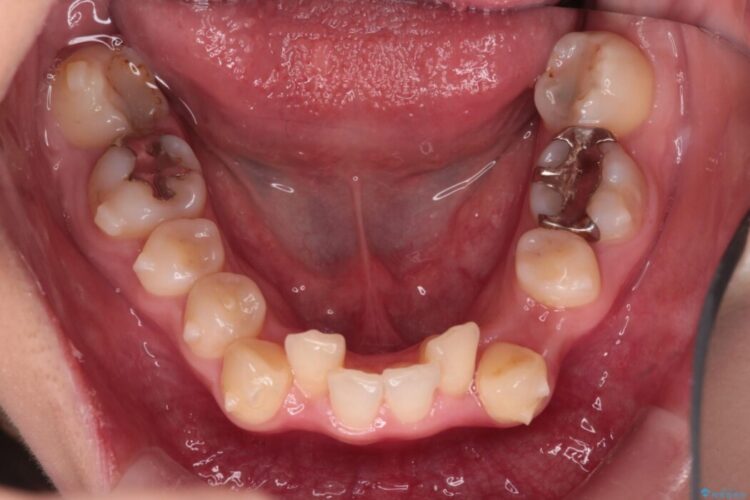

飛び出るように生えた八重歯をなおしたいとの主訴で来院されました。

インビザラインによる矯正を希望され、今回は移動距離が少なくなるように犬歯を抜歯し、歯肉退縮や装置の特性を考慮した治療計画としました。

下顎に関しては、半年ほどワイヤー矯正にてリカバリーを行なっております。